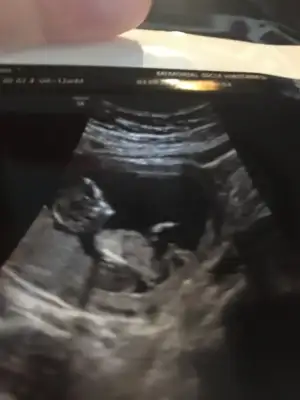

Kızlar burada 11+4 tü doktor önce kiz dedi sonra erkek dedi yorum yapabilir misiniz bana da